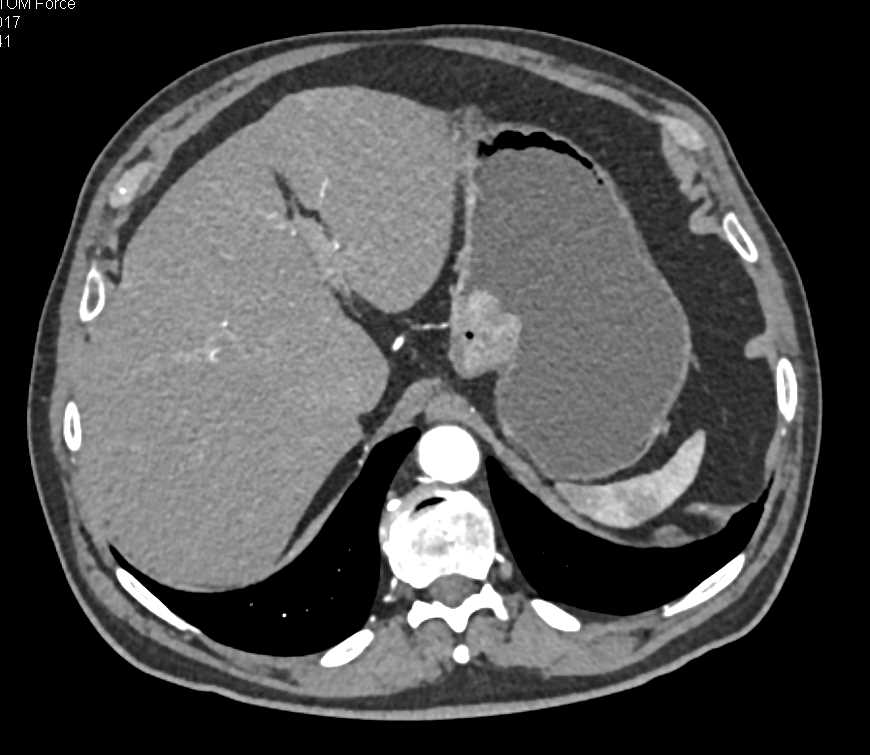

Perforated Gastric Ulcer